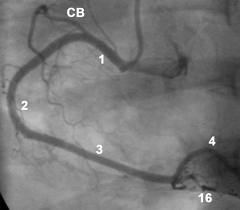

El corazón recibe sangre por vía de las 3 arterias coronarias.

La arteria coronaria principal izquierda, se bifurca en: 1) la arteria descendiente anterior y 2)la arteria circunfleja. Estas aún se dividen en otras ramas más pequeñas. La tercera arteria coronaria es: 3). la arteria coronaria derecha, que también se bifurca en otras ramas más pequeñas. Todas estas arterias y sus ramas son las responsables de suministrarle sangre al músculo del corazón.

y arteria circunfleja